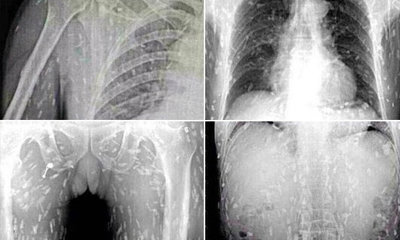

ภาพเอกซเรย์พยาธิเต็มตัว เกิดได้จริง

มีรายงานว่า เฟซบุ๊ก Jessada Denduangboripant ของ นายเจษฎา เด่นดวงบริพันธุ์ อาจารย์ประจำภาคชีววิทยา คณะวิทยาศาสตร์ จุฬาลงกรณ์มหาวิทยาลัย โพสต์ข้อความอธิบาย กรณีที่มีภาพเอกซเรย์ของชายชาวจีนรายหนึ่งซึ่งเจอพยาธิกระจายทั่วทั้งตัว ว่า เรื่องนี้เป็นเรื่องที่เกิดได้จริง ส่วนประเด็นที่มีการระบุว่า พยาธิในร่างกายชายคนนี้มาจากปลาดิบนั้นไม่ยืนยัน แต่รับว่า พยาธิตัวตืดของปลานั้นมีจริง ส่วนการที่เอกซเรย์เห็นพยาธิได้ เป็นเพราะร่างกายสร้างแคลเซียมเพื่อมาต้านพยาธินั่นเอง

“ภาพเอ็กซเรย์คนจีนเจอพยาธิทั้งตัว เรื่องจริงหรือไม่” ….

เรื่องจริงครับ เป็นภาพเอ็กซเรย์ของคนที่มีพยาธิตัวตืด กระจายไปตามเส้นเลือดไปทั่วร่างกาย แค่สิ่งที่เอ็กซเรย์เห็นนั้นเรียกว่า cysticercosis คือเป็นแคลเซี่ยมของร่างกายเราที่สร้างขึ้นมาต่อต้านกับพยาธิ จึงทำให้เอ็กซเรย์เห็นได้

ตามข่าวเชื่อว่าพยาธิตัวตืดนี้มากับการกินเนื้อปลาดิบๆของปลาน้ำจืด (บ้านเราก็มีคนไข้แบบนี้เช่นกัน จากตัวตืดหมู) …. วิธีการป้องกันที่ดีที่สุดคือ การทำให้สุกเสียก่อน หรือเอาปลาดิบนั้นแช่แข็งอุณหภูมิติดลบ 15 องศา สัก 4 วันครับ”

นอกจากนี้ นายเจษฎา ยังระบุเพิ่มเติมเมื่อมีคนมาโต้แย้งด้วยว่า ตนเพียงบอกว่าภาพนั้นเป็นภาพพยาธิจริง และตามข่าวจากสำนักข่าวต่างประเทศ แพทย์ระบุว่ามาจากปลา จึงตอบข้อสงสัยที่ว่าในปลามีพยาธิตัวตืดเช่นเดียวกับหมู แต่ไม่ได้ฟันธงว่าคนจีนรายนี้เป็นโรคจากพยาธิตัวตืดปลาจริงหรือไม่